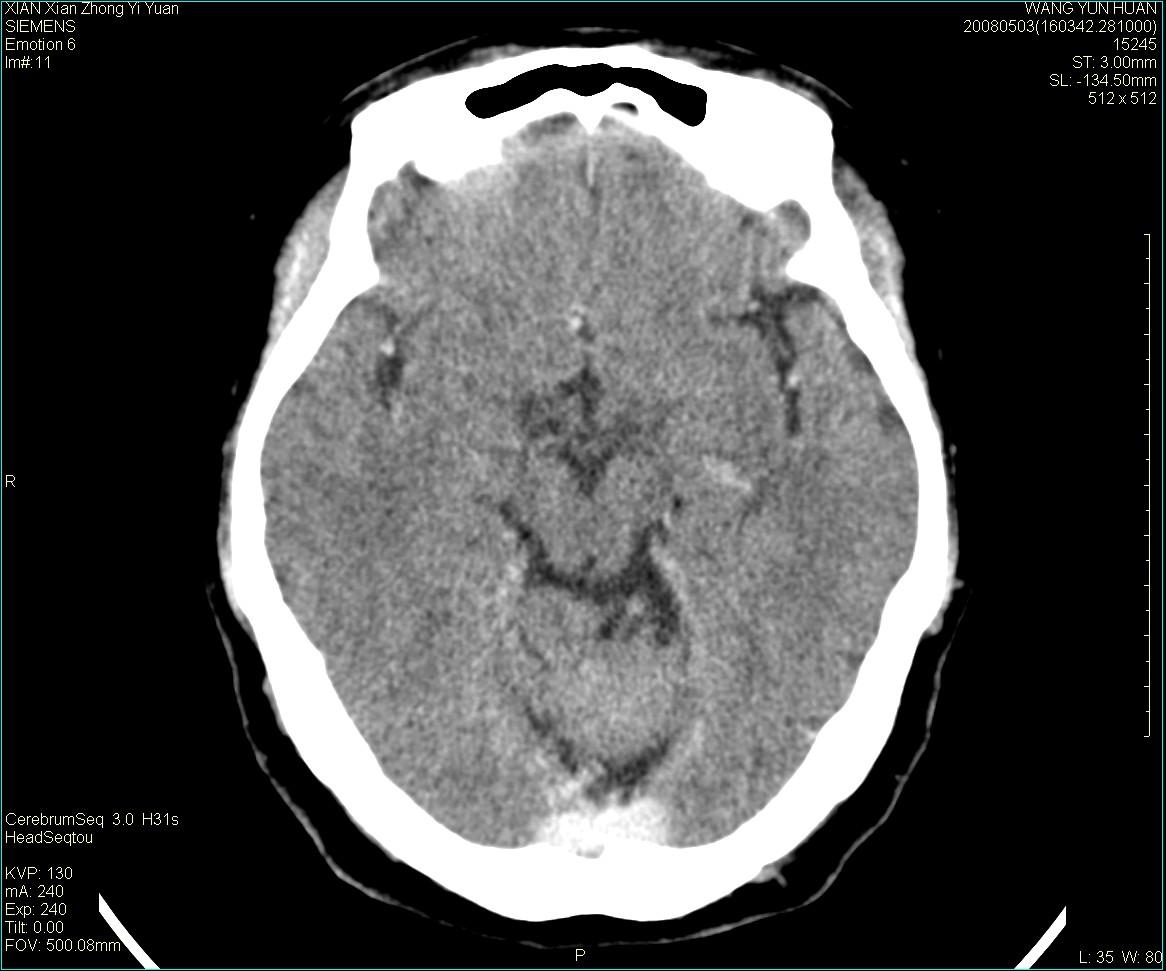

标题: CT13219:(补充强化)请会诊,患者女,60岁,头晕,大家看 [打印本页]

标题: CT13219:(补充强化)请会诊,患者女,60岁,头晕,大家看

病灶显示轻度强化,ct增加4hu左右,大家看是什么肿瘤.

强化后动脉期及延迟2分钟,五分钟图像

小脑蚓部囊型肿块,内有实性结节及钙化点。增强后囊壁及结节轻度强化。

考虑蚓部星形细胞瘤(ⅱ级可能性大)。

小脑蚓部肿块,周围无明显占位效应及水肿带,增强轻度强化,考虑低分级星形细胞瘤。